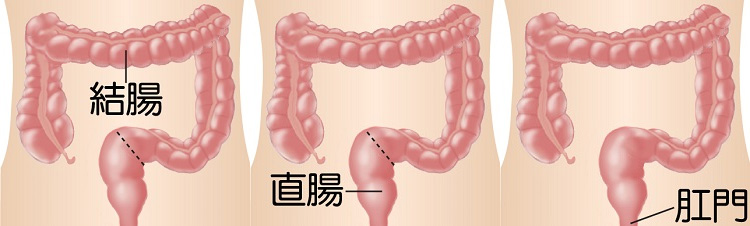

大腸癌是本港第3常見的癌症,亦是本港致命癌症中的第2位。大腸癌篩查可及早識別未出現病徵的大腸癌患者或高危人士,讓其及早接受治療,大大提高治癒率,而在大腸鏡檢查過程中切除大腸腺瘤,則可避免腺瘤演變成癌症。經計劃確診大腸癌的個案中,約2400宗已進行初步分析,結果顯示約56%屬於早期個案,治癒率較高。